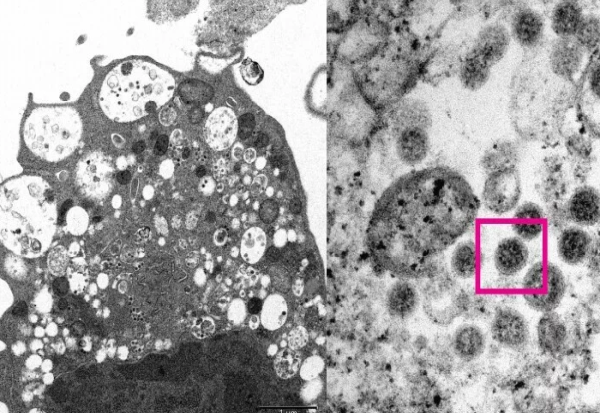

Универзитетот во Хонгконг во средата ја објави првата фотографија од омикрон направена со помош на електронски микроскоп.

Медицинските научници, вклучително и патолози и виролози, успеаја да направат електронска микрографска фотографија на бубрежна клетка на мајмун (Веро Е6) откако мајмунот беше заразен со омикрон.

Споменатиот универзитет објави фотографии од омикрон со мало и големо зголемување.

При мало зголемување, сликата покажува оштетување на клетките со отечени везикули кои содржат мали црни вирусни честички, објаснуваат научниците.

Сликата со големо зголемување покажува множества од вирусни честички со шилци на нивната површина.